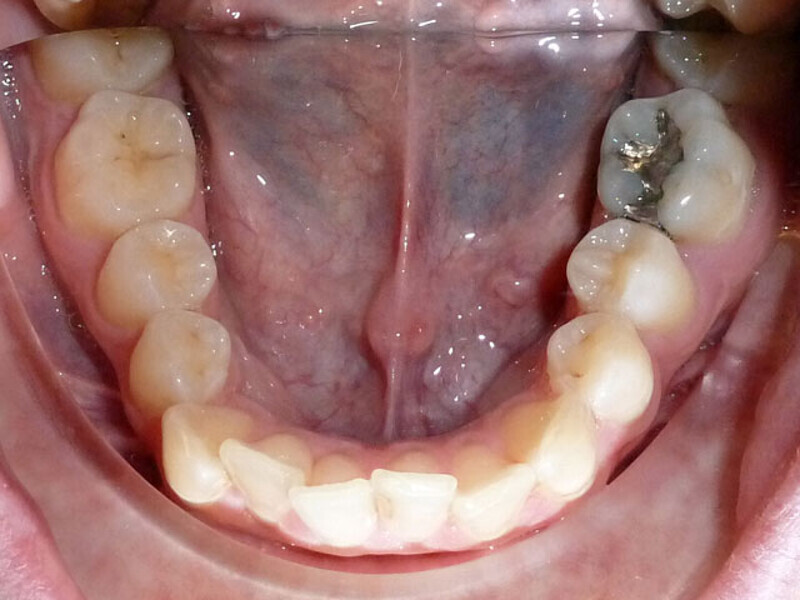

ClearCorrect treatment of crowding